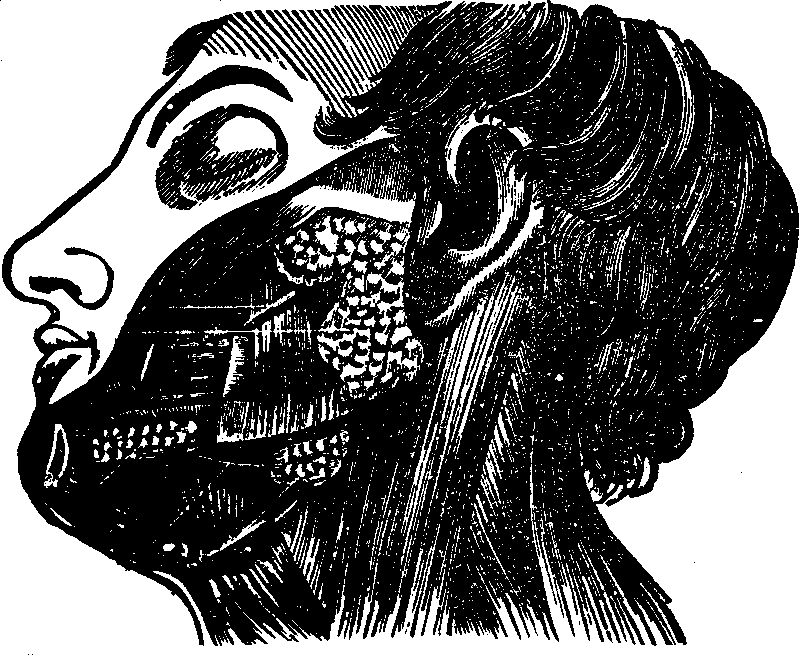

Fig.

27. The salivary glands. The largest one, near the ear, is the parotid

gland. The next below it is the submaxillary gland. The one under the

tongue is the sublingual gland.

The Salivary Glands are six in number, three on each side of the mouth. Their function is to secrete a fluid called saliva, which aids in mastication. The largest of these glands, the Parotid, is situated in front and below the ear; its structure, like that of all the salivary glands, is cellular. The Submaxillary gland is circular in form, and situated midway between the [pg 39]angle of the lower jaw and the middle of the chin. The Sublingual is a long flattened gland, and, as its name indicates, is located below the tongue, which when elevated, discloses the saliva issuing from its porous openings.